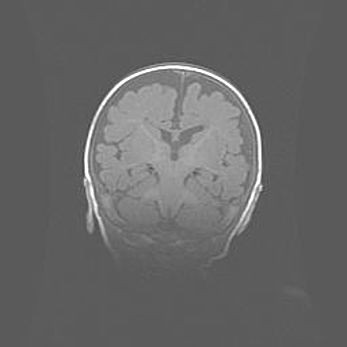

Церебральная ишемия II.

Возраст: 5 дней

Вес: 3400 г

Пол: женский

Окружность головы: 35 см

Срок гестации: 39 недель

Церебральная ишемия – это заболевание, характеризующееся недостаточностью (гипоксией) либо полным прекращением (аноксией) снабжения мозга кислородом по причине закупорки одного или нескольких сосудов. Это приводит к  что метаболическим расстройствам различной степени тяжести в тканях головного мозга, развитию коагуляционных некрозов и гибели нейронов.